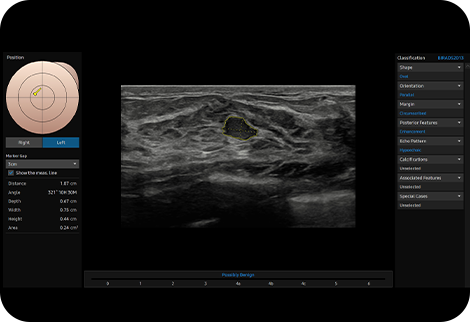

Analyze selected breast lesions and

report breast assessment

S-Detect™ for Breast ¹, analyzes selected lesions in the breast ultrasound study and shows the analysis data, applies BI-RADS ATLAS* to provide standardized reporting; and helps diagnosis with the streamlined workflow.

* Breast Imaging-Reporting and Data System, Atlas

It is a registered trademark of ACR and all rights reserved by ACR.